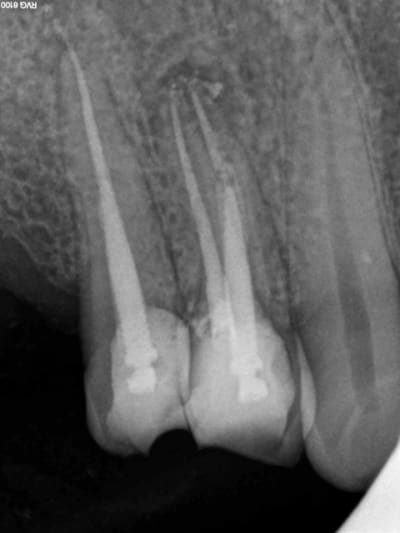

Aujourd'hui patient en urgence ca tombe bien pour une fois synchro avec un lapin.

45 mn de turbinage intensif 2 endos + 2 SC 33; On cote comment les radios ?

Z6, SC 20, Z3,Z3, SC20, Z3, Z3, SC 33, Z3, SC 33, Z3 ?

Tssss, Z6 radio de diagnostic, endo Z3 + Z3 par endo, SC33 radios de controle Z3, 1 par acte.

Avant c'était Z6 par séance quel que soit le nombre de clichés. Je n'ai pas fait les 2 endos en meme temps simplement la première à été faite en mode turbo, j'avais donc du temps en rab et j'ai fait la seconde après. A la limite un Z 3 de trop sur les SC 33.

Pour les endo, c'est un Z6 Rx de diagnostic, et un Z3 Rx de contrôle finale, non? Or les deux dents sont adjacentes, c'est donc 1 Z6 + 1Z3 pour les deux endos... Et 1 Z3 pour les deux SC33.